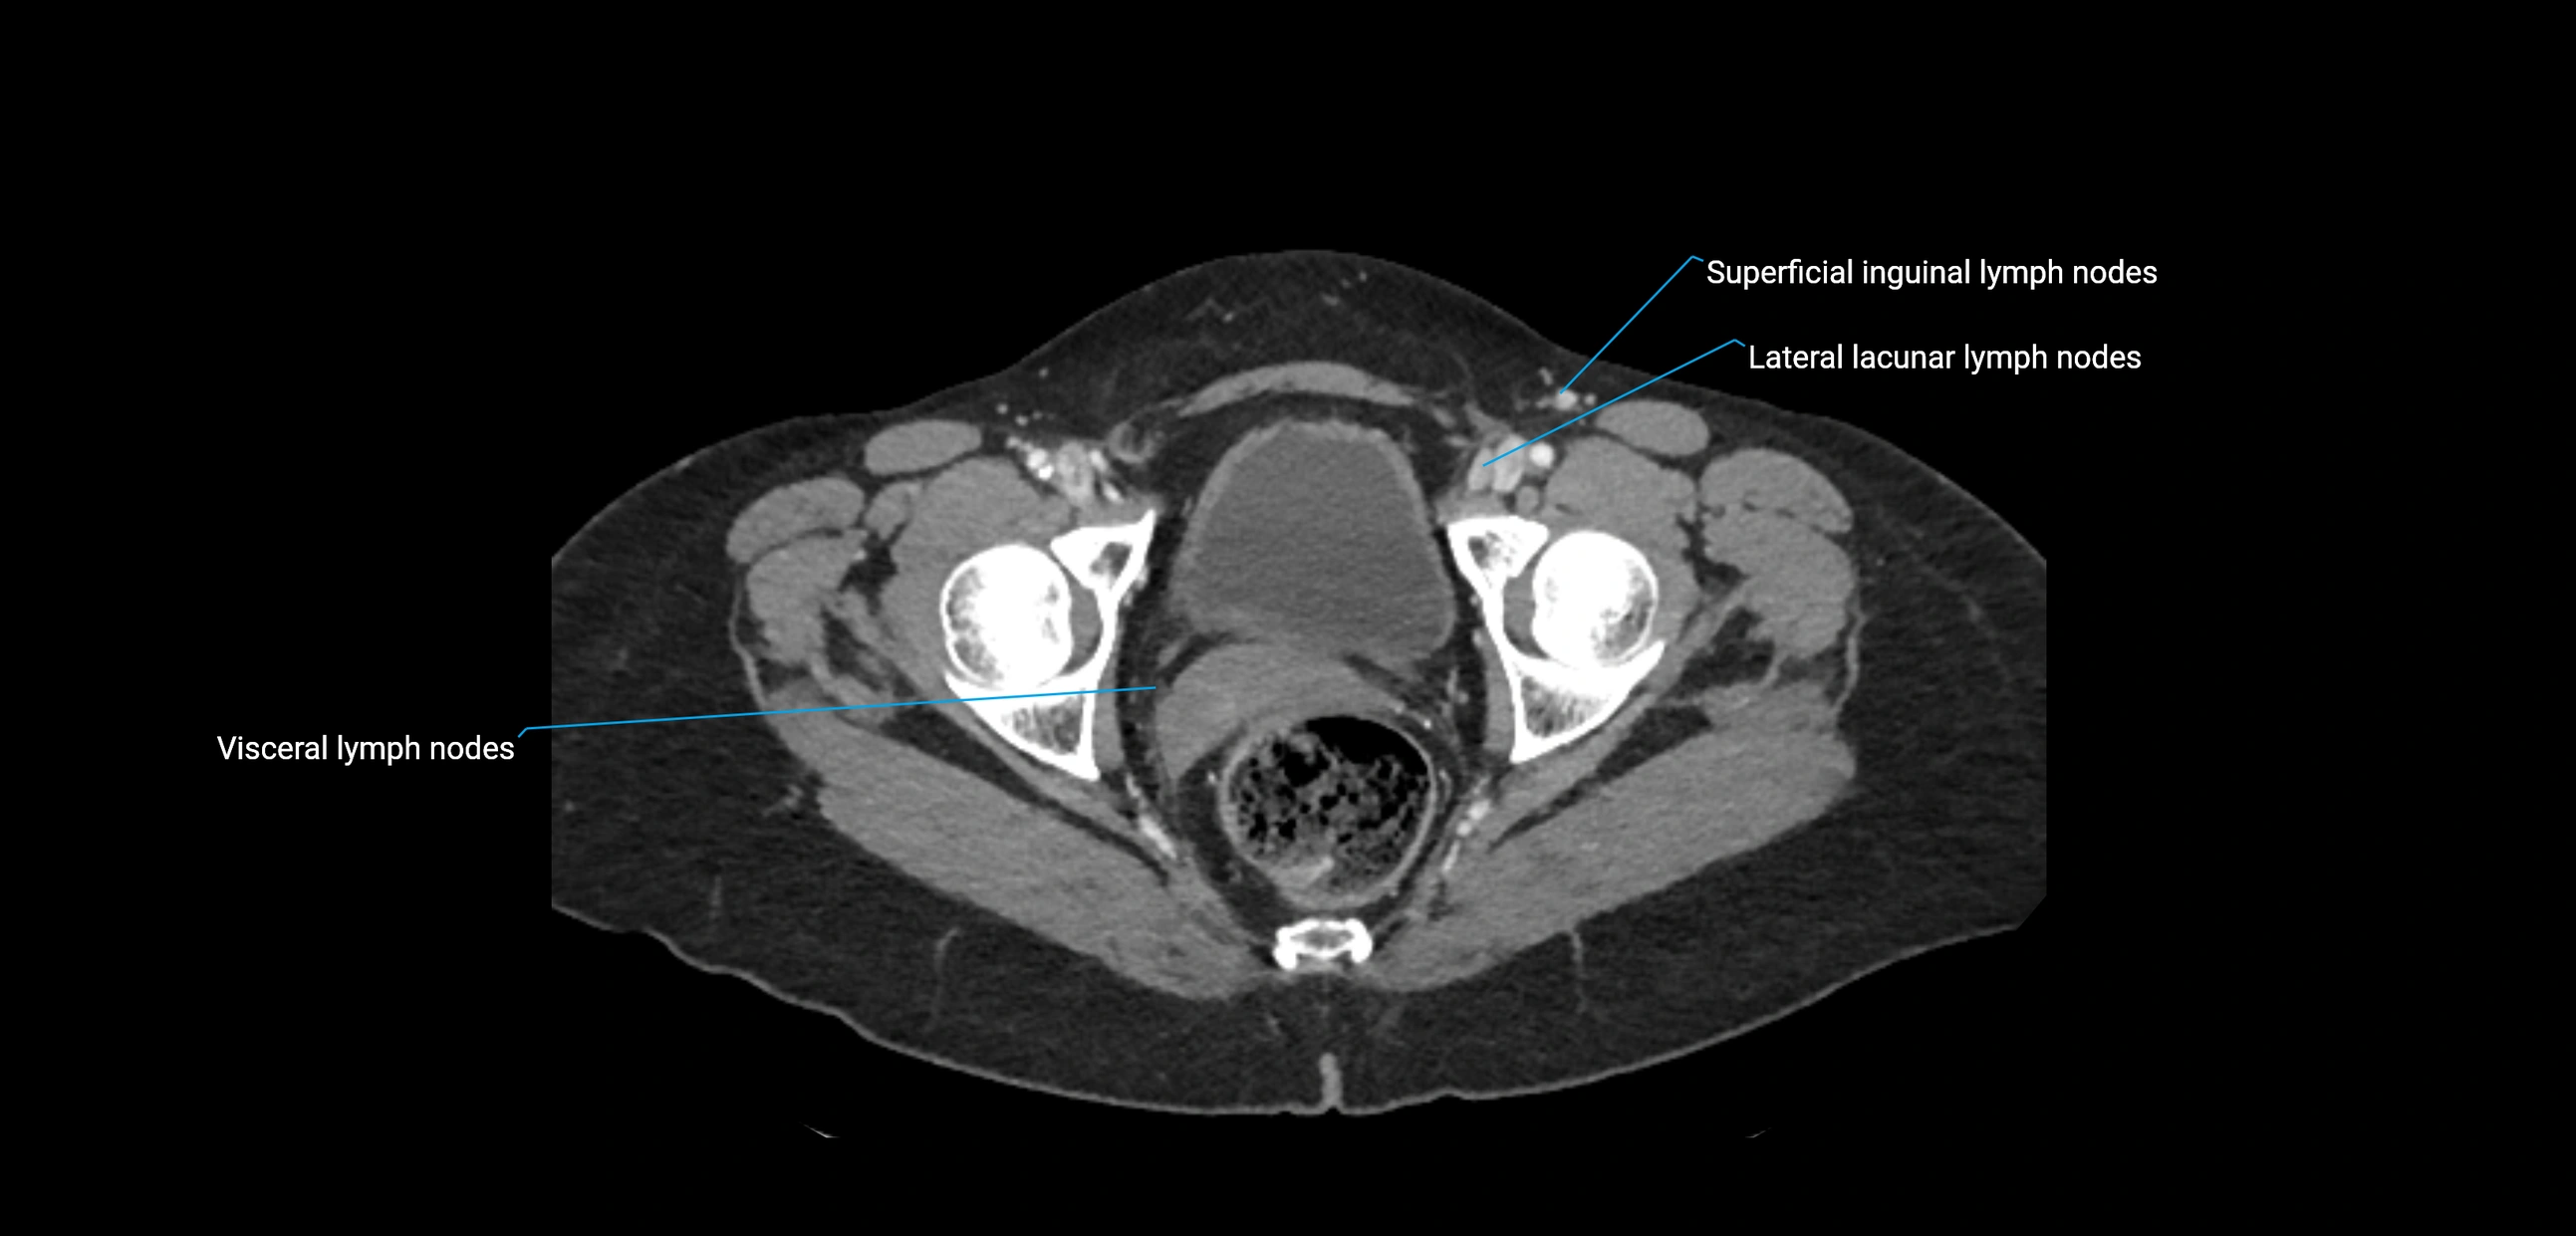

CT Appearance

CT Pre-Contrast:

• Nodes appear as soft-tissue density nodules adjacent to the aorta and IVC

CT Post-Contrast:

• Normal nodes enhance homogeneously

• Malignant nodes may show heterogeneous enhancement, central necrosis, or conglomerate formation

• Size >1 cm short axis is suspicious, though morphology and distribution are equally important

CT image

image